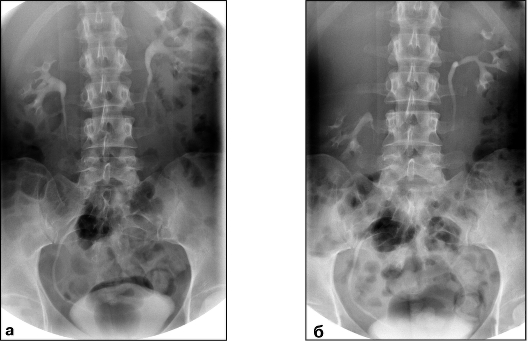

Экскреторная урография при нефроптозе: диагностические изображения